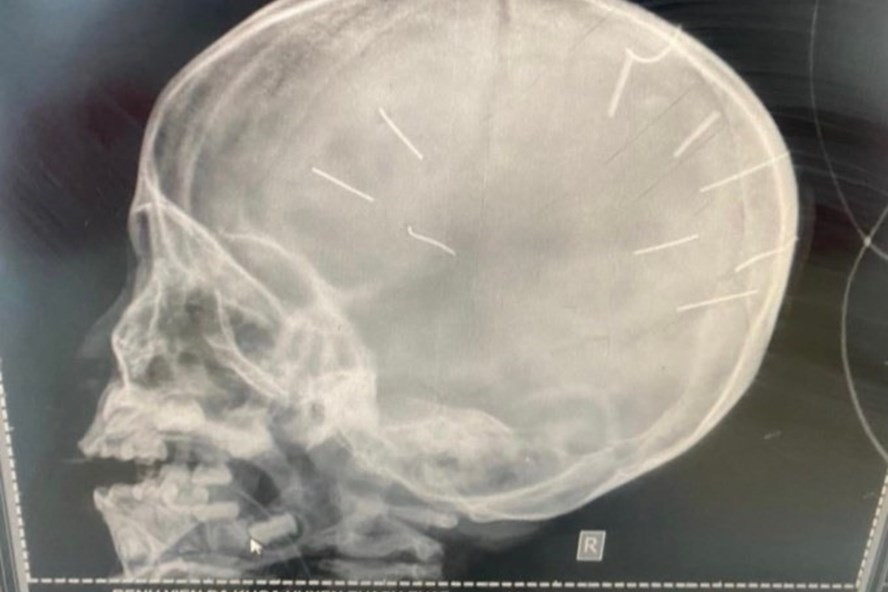

| Hình ảnh nhiều dị vật găm vào đầu bé gái 3 tuổi nghi bạo hành. Ảnh: Gia đình cung cấp. |

Ông Kiên cũng cho biết thêm, thông tin từ Bệnh viện Xanh Pôn mà ông có được, sau khi phía bệnh viện này tiến hành chụp cắt lớp, nhận thấy có những hình ảnh như đinh bắn vào sọ.

"Trên hình ảnh phim chụp X-Quang cho thấy có dị vật giống 9 đinh được bắn vào sọ bé gái 3 tuổi này. Hiện tình trạng bệnh nhân nặng, tiên lượng tử vong rất cao”, ông Kiên cho hay.

Liên quan đến vụ việc, Tiến sĩ, luật sư Đặng Văn Cường - Đoàn Luật sư TP Hà Nội cho rằng, thông tin về cháu bé quá sốc với nhiều người. Nếu kết quả xác minh đúng là những chiếc đinh đã đâm vào đầu cháu bé ở nhiều phía khác nhau như vậy thì chắc chắn là có tác động ngoại lực chứ không phải là một vụ tai nạn.

Luật sư Nguyễn Anh Thơm - Đoàn luật sư TP.Hà Nội cho rằng, theo thông tin các cơ quan chức năng xác định, cháu bé khi vào viện trong tình trạng hôn mê, co giật, chụp phim sọ não thấy có khoảng 9 vật nghi là đinh bắn, có thể thấy cháu bé bị đinh găm vào đầu là do tác động trực tiếp của loại hung khí nguy hiểm gây nên.